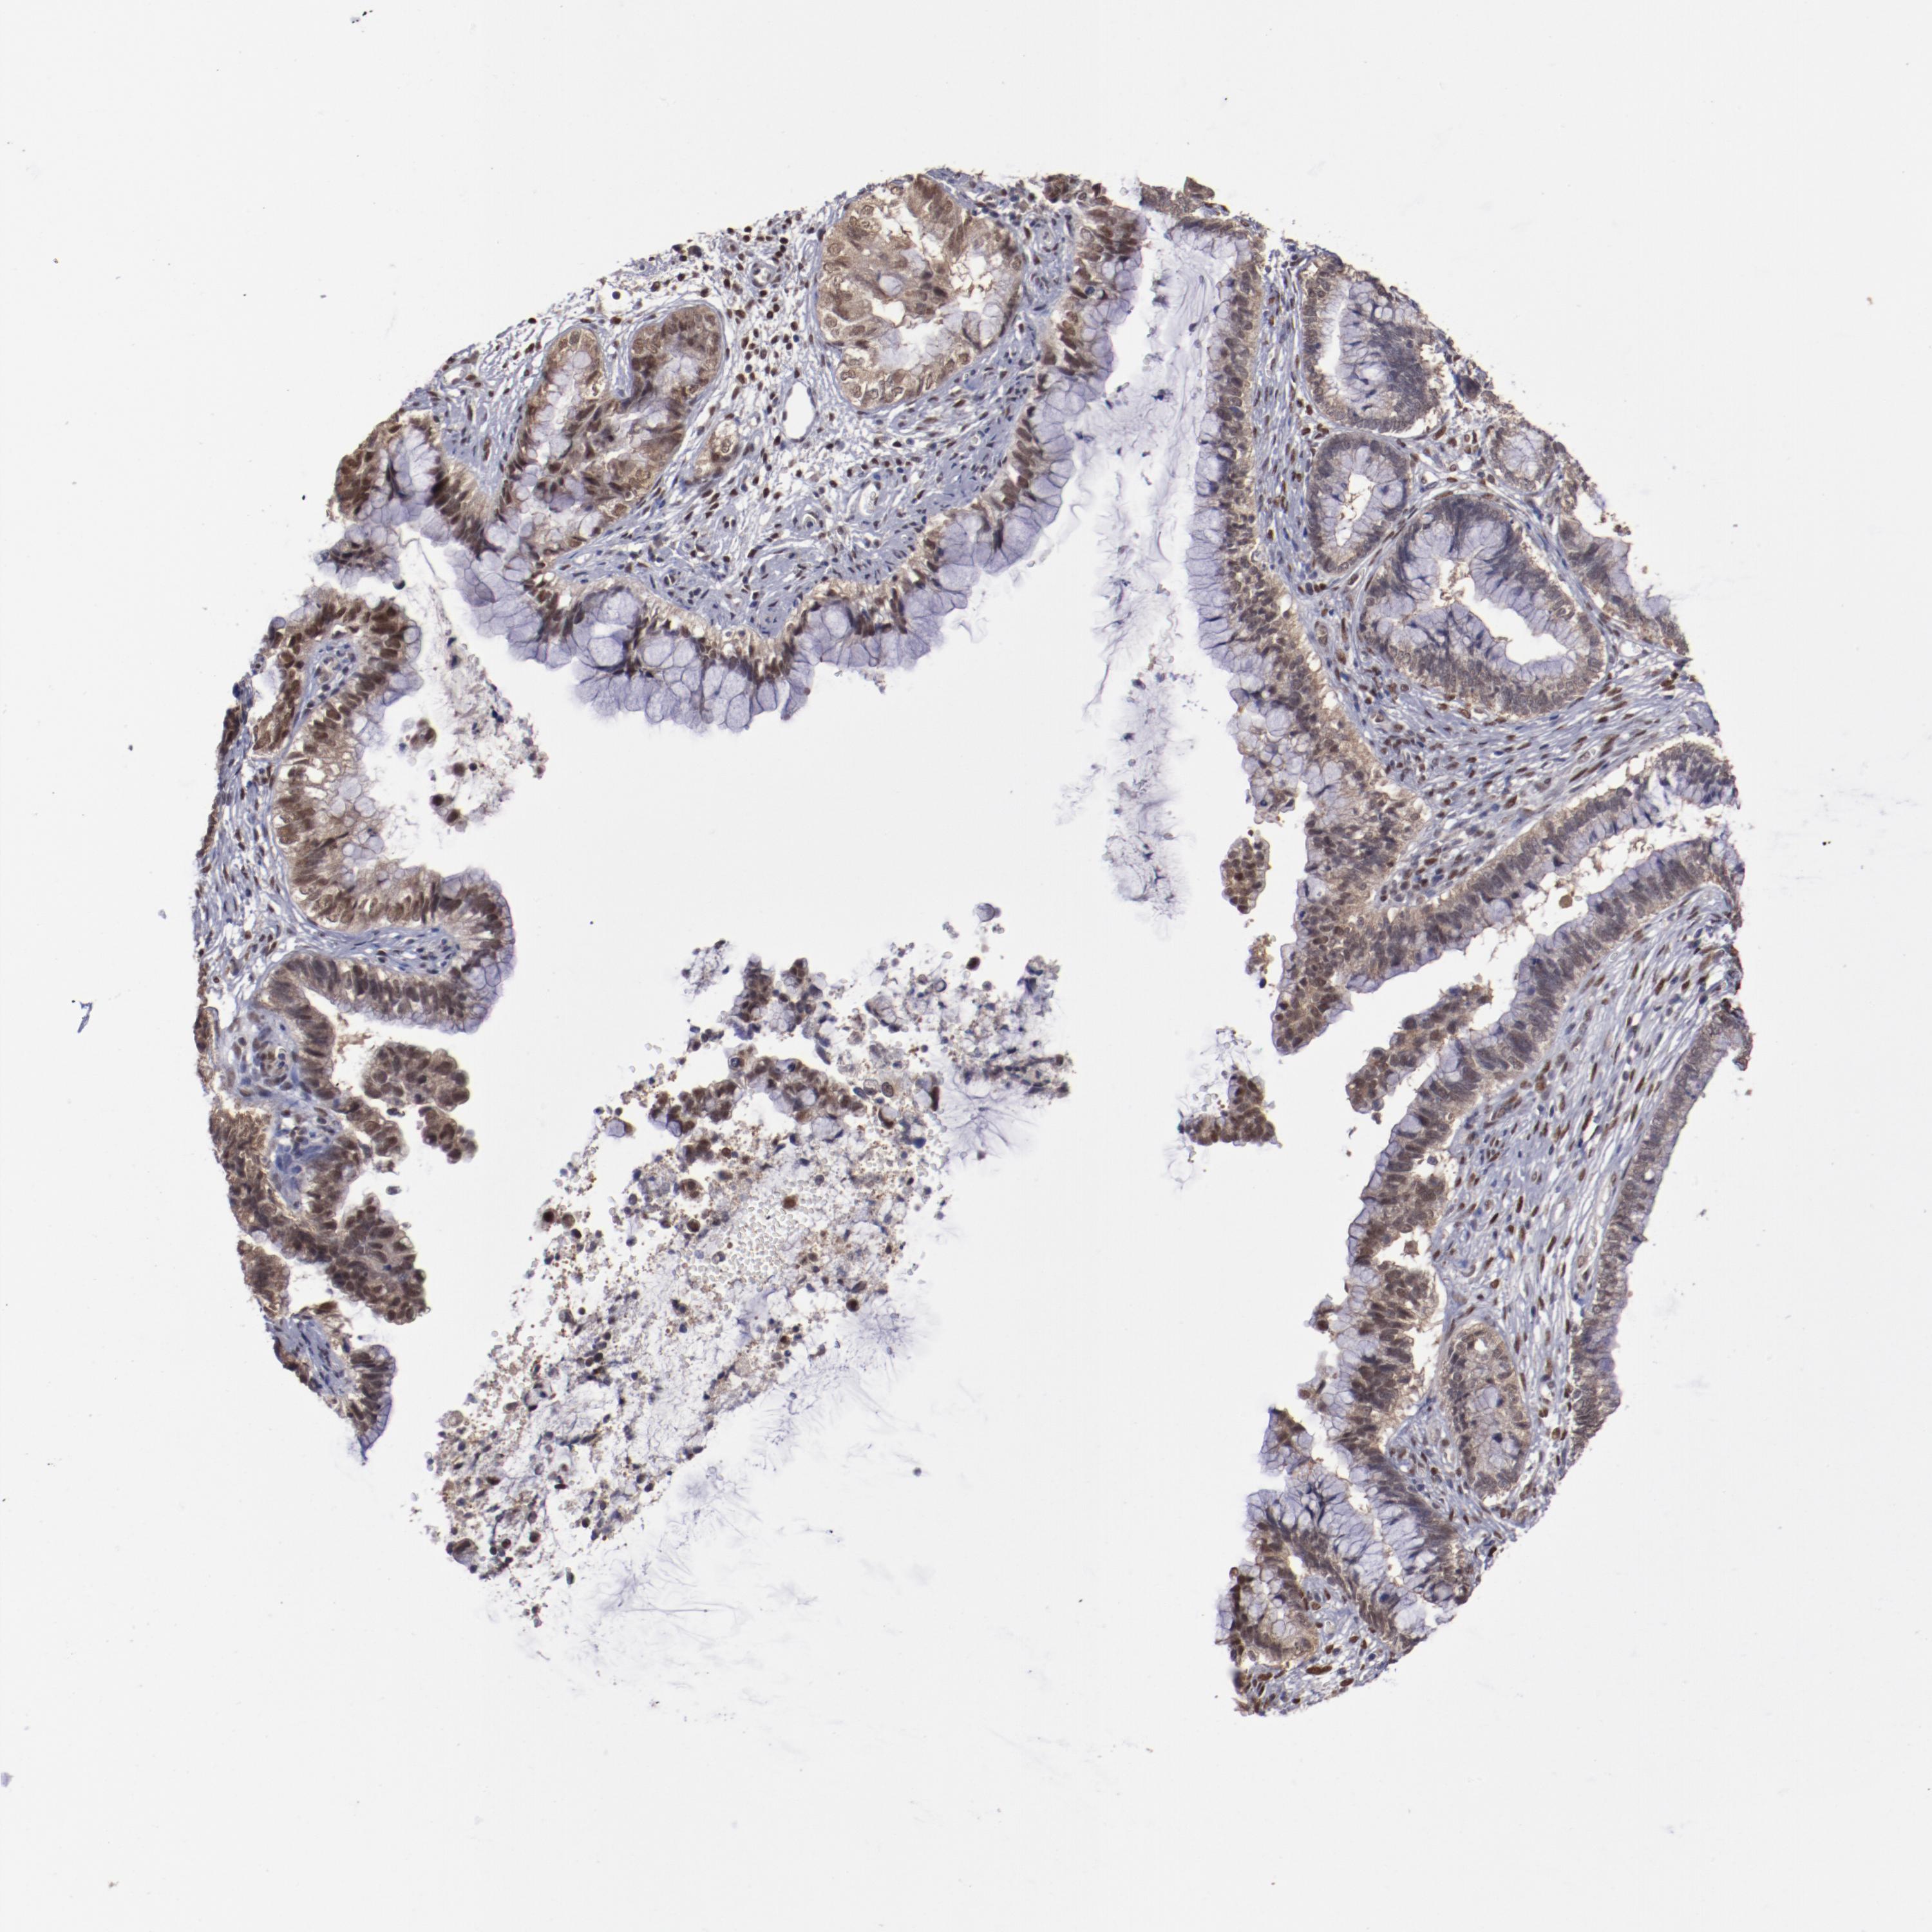

CERVICAL CANCER - Protein expressioni

A mouse-over function shows sample information and annotation data. Click on an image to view it in a full screen mode. Samples can be filtered based on level of antibody staining by selecting one or several of the following categories: high, medium, low and not detected. The assay and annotation is described here.

Note that samples used for immunohistochemistry by the Human Protein Atlas do not correspond to samples in the TCGA dataset.

Antibody stainingi

Antibody staining in the annotated cell types in the current human tissue is reported as not detected, low, medium, or high, based on conventional immunohistochemistry profiling in selected tissues. This score is based on the combination of the staining intensity and fraction of stained cells.

Each image is clickable and will lead to virtual microscopy that enables deeper exploration of all samples and also displays staining intensity scores, fraction scores and subcellular localization as well as patient and tissue information for each sample.

Antibody HPA001759

Antibody CAB004318

Staining

High

Medium

Low

Not detected

Intensity

Strong

Moderate

Weak

Negative

Quantity

>75%

75%-25%

<25%

None

Location

Nuclear

Cytoplasmic/membranous

Cytoplasmic/membranous,nuclear

Squamous cell carcinoma, NOS

Adenocarcinoma, NOS